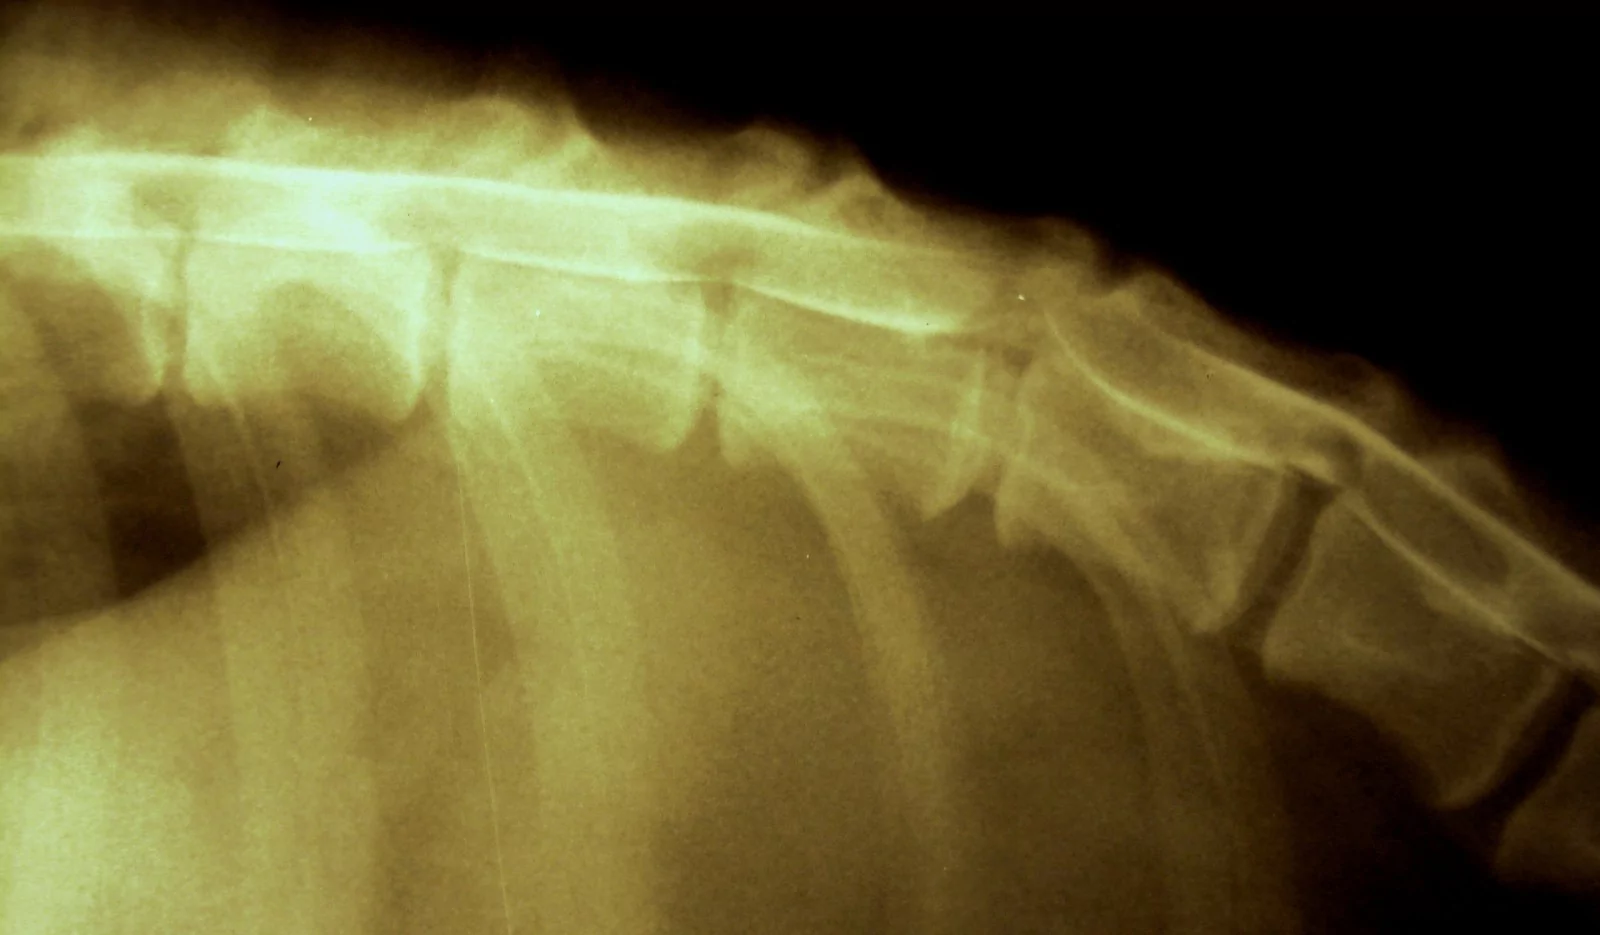

Рентгенографическое исследование может быть информативно в выявлении данной проблемы, но оно не даёт точной локализации выпавшего содержимого грыжи.

К признакам болезни межпозвонковых дисков Хансен тип 1 при рентгенографии относятся сужение межпозвонкового пространства, межпозвонковых отверстий и пространства между суставными отростками. Если ядро выпавшего диска подверглось обызвествлению, то иногда его можно заметить в позвоночном канале, но это бывает крайне редко. При заболевании межпозвонковых дисков Хансен тип 2 на рентгене можно наблюдать другую картину. При хронических проблемах типичными признаками, помимо сужения межпозвонкового пространства и отверстий, являются склероз суставных пластинок позвонков, образование остеофитов, спондилез и прочее. Особенно выражено это при люмбо-сокральном стенозе («синдром конского хвоста»).